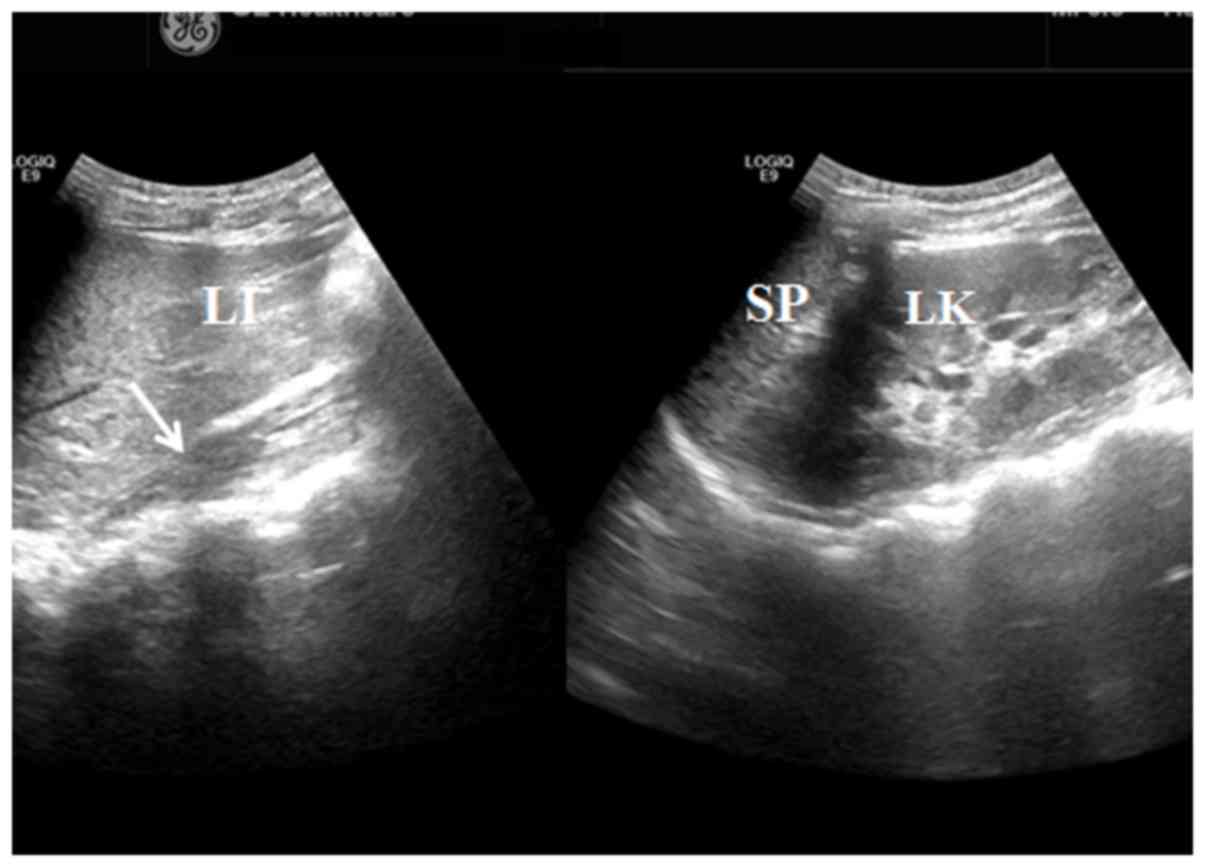

Figure 4.

Sonogram obtained from double waist oblique coronal sections from a 14-year-old patient identifying the absence of the right kidney (white arrow; left side of the figure). The left kidney was normal (right side of the figure). LI, liver; SP, spleen; LK, left kidney.